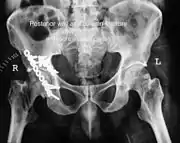

Acetabular fracture

| Acetabular fracture as seen on plain X-ray |

Fractures of the acetabulum occur when the head of the femur is driven into the pelvis. This injury is caused by a blow to either the side or front of the knee and often occurs as a dashboard injury accompanied by a fracture of the femur.[1]